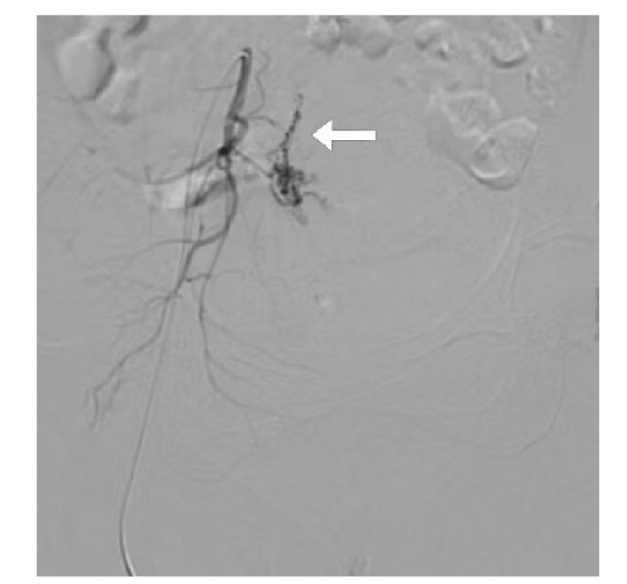

先天性心脏病术后稽留流产术中急性失血性休克属于妇产科与心血管科交叉的罕见疑难并发症,需兼顾先天性心脏病患者的特殊生理状态与稽留流产的病理特征。报告1例先天性心脏病术后稽留流产术中出现急性失血性休克患者,患者在诊断性刮宫术中发生失血性休克后急诊行子宫动脉栓塞术,术后患者病情平稳后再次行超声监测下钳刮术,顺利清除宫腔残留组织。临床上对宫腔内占位性病变性质不明确者,应通过病史、影像学检查及术后病理综合分析明确诊断。罕见疑难病例诊治中需充分利用医疗资源,践行科学、合理、人性化的诊疗思路,最大限度保障患者生命安全。